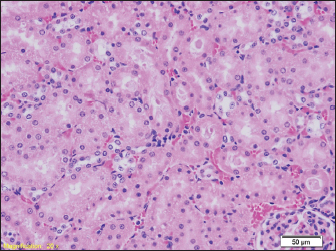

Signs of hydropic and vacuolar degeneration can be seen in the kidney samples of all groups of rats, and signs of acute tubular necrosis can be seen in one of the samples (group G2) (Figs. 7 and 8).

Fig. 7. Kidney parenchyma also shows signs of congestion (HE, ×40). Signs of hydropic and vacuolar degeneration can be seen in the kidney samples of all groups of rats, and signs of acute tubular necrosis can be seen in one of the samples (group G2) (Figs. 7 and 8).

Signs of hydropic and vacuolar degeneration can be seen in the kidney samples of all groups of rats, and signs of acute tubular necrosis can be seen in one of the samples (group G1).

The pathohistological findings of the kidneys in all examined groups indicate hydropic and vacuolar degeneration of the epithelial cells of the renal tubules, and the pathohistological findings of the brain in all groups show signs of pericellular and perivascular edema. In our study, we did not find diatoms in the kidneys. Previous studies prove that the number of diatoms found may be lower than expected, as in liver samples. Since the middle of the last century, there have been certain disagreements among numerous authors about the reliability of diatom findings in internal organs such as the kidney, liver, or bone marrow. The reason for this is the high rate of occurrence of false positive findings (Timperman, 1969).

The results of the pathohistological examination of the kidneys in our study coincide with those of other authors. In previous studies, after drowning, signs of glomerular enlargement with hypercellular changes were found on the kidneys, signs of degeneration were present in the tubules, such as their uneven expansion and edema of the cells of the tubular walls, and in the interstitium, there were congested capillaries were present (Ibrahim et al., 2022). Seong et al. (2012) also reported signs of acute tubular necrosis after drowning (Seong et al., 2012).